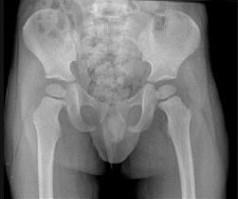

男,请根据其正常骨盆影像图像,判断其最可能的年龄 ( )A、12岁左右B、10岁左右C、8岁左右D、6岁左右E、2岁左右

问题 男,请根据其正常骨盆影像图像,判断其最可能的年龄 ( )

选项 A、12岁左右 B、10岁左右 C、8岁左右 D、6岁左右 E、2岁左右

答案 E